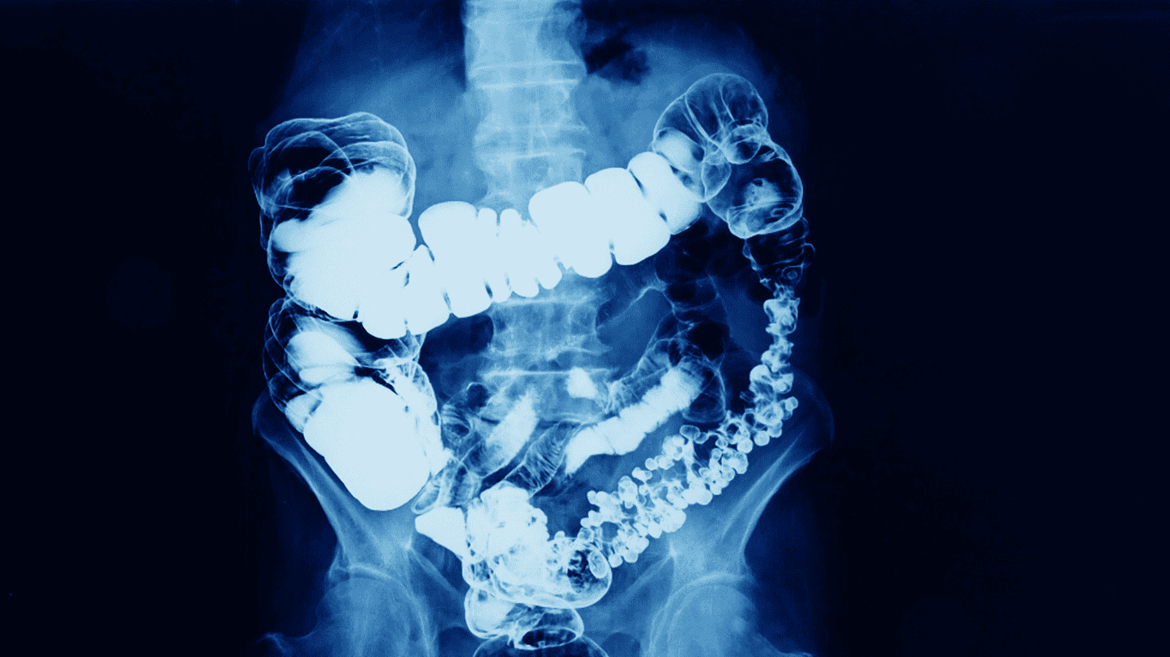

- 大腸灌注:如硫酸鋇顯影劑。

- 硫酸鋇顯影劑:常用於消化道X光檢查及CT掃描。